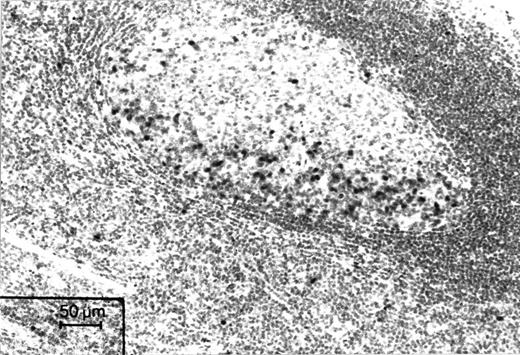

Immunohistochemical staining of a microwave-processed paraffin section of a formalin-fixed human tonsil with Ki-S2. Cell nuclei in the dark zone of a germinal center, which harbors proliferating cells, are strongly positive. APAAP staining.

Immunoreactivity of Ki-S2 in normal tissue.Ki-S2 was shown to be a mouse monoclonal IgG1 antibody that specifically detects an antigen in the nuclei of proliferating cells in sections of frozen and paraffin-embedded tissues. There was no difference in the number of positive cells and in the intensity of the reaction between frozen sections and paraffin-embedded samples. The distribution of this nuclear antigen in normal human tissue was found to be restricted to sites harboring cycling cells, such as the germinal centers of lymphoid tissue (Fig 1). Nonspecific cross-reactivities in normal human tissue were not observed. Extensive immunohistochemical investigation of all normal tissue types showed that p100 and the Ki-S2 antibody are highly specific to the nuclei of cycling cells in characteristic tissue sites. In the epithelial coverings, a few basal epithelial cells and a moderate number of suprabasal epithelial cells showed a positive reaction. In the mucosa of the gastrointestinal tract, Ki-S2–positive cells were restricted to the lower part of the crypts. In lymphoid tissue, the dark zone of the germinal centers of lymphoid B follicles was highly reactive, whereas the number of positive cells did not exceed 5% in other areas of the lymph nodes. In testicular tissue, spermatogonia reacted strongly, whereas mature spermatozoa were invariably negative. In the bone marrow, promyelocytes, myelocytes, proerythroblasts, and erythroblasts (E1 and E2) were positive, whereas mature granulocytic cells and erythroblasts were consistently negative. Normal nonstimulated PBMC were negative for Ki-S2 and Ki-S5, and only occasional cells (<1%) showed faint nuclear reactivity. After stimulation of PBMC with PHA, the expression of the Ki-S2 antigen increased, paralleling that of the Ki-S5–reactive Ki-67 antigen. On day 3, 25% ± 4% of the stimulated cells expressed the Ki-S2 antigen. The Ki-S2 antigen expression correlated positively with the expression of the Ki-67 antigen determined by the MoAb Ki-S5 (r = .89, P < .01; Table 1).